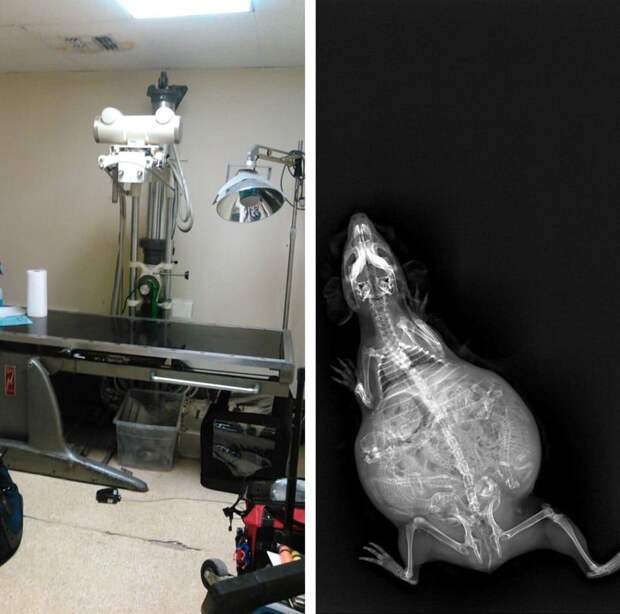

Мы все прекрасно представляем, как проходит беременность человека, и благодаря современным технологиям можем увидеть ребёнка в утробе матери на самых ранних стадиях, с разных ракурсов и даже в трёхмерной проекции. Но а как же выглядит беременность у братьев наших меньших? Специалисты, которые по долгу своей работы наблюдают животных, готовых принести потомство, поделились этими удивительными рентгеновскими и ультразвуковыми снимками.

8. Беременная морская свинка

9. И ещё одна